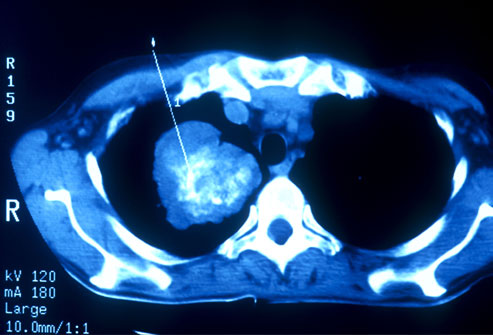

폐암의 진단은 주로 의사가 환자의 증상, 진료 이력, 가족 질환 여부, 기침 상태, 체중 변화, 기침에서 나오는 가래의 색깔 등을 질문하고, 폐 X선 촬영, 생리학적 검사, 폐기능 검사, 조영술 등을 통해 진단합니다.